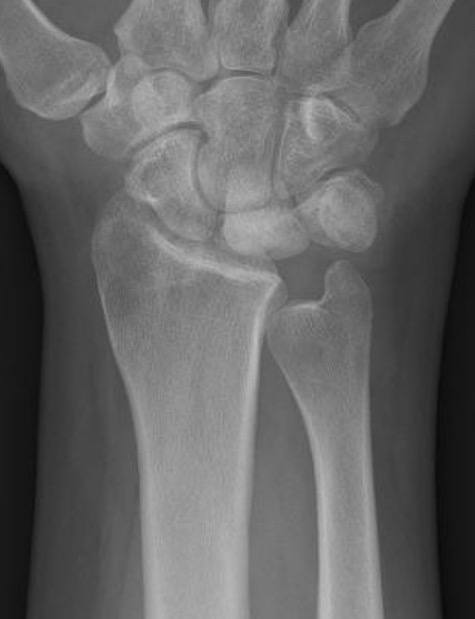

Xray

Progressive changes of AVN

- sclerosis

- fragmentation / fracture / flattenging

- midcarpal collapse: scaphoid flexion / capitate descent

- radiocarpal and midcarpal osteoarthritis

Lichtmann Classification

| Stage II | Stage IIIA |

|---|---|

| Sclerosis |

Collapse / fragmentation Normal carpal height |

| Stage IIIB | Stage IV |

|

Collapse / fragmentation Scaphoid flexed / Capitate migrates proximally |

Pancarpal osteoarthritis |

Ulna Variance

Supination and pronation alter variance

90 / 90 view (elbow 90° / shoulder abducted 90°)

- neutral supination / pronation

- PA film with wrist in neutral

- line from lunate fossa and ulna head

Ulna neutral

Ulna positive

Ulna negative